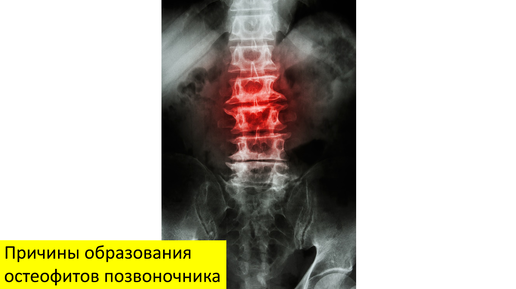

Причины образования остеофитов позвоночника

Причины образования костных шпор позвоночника